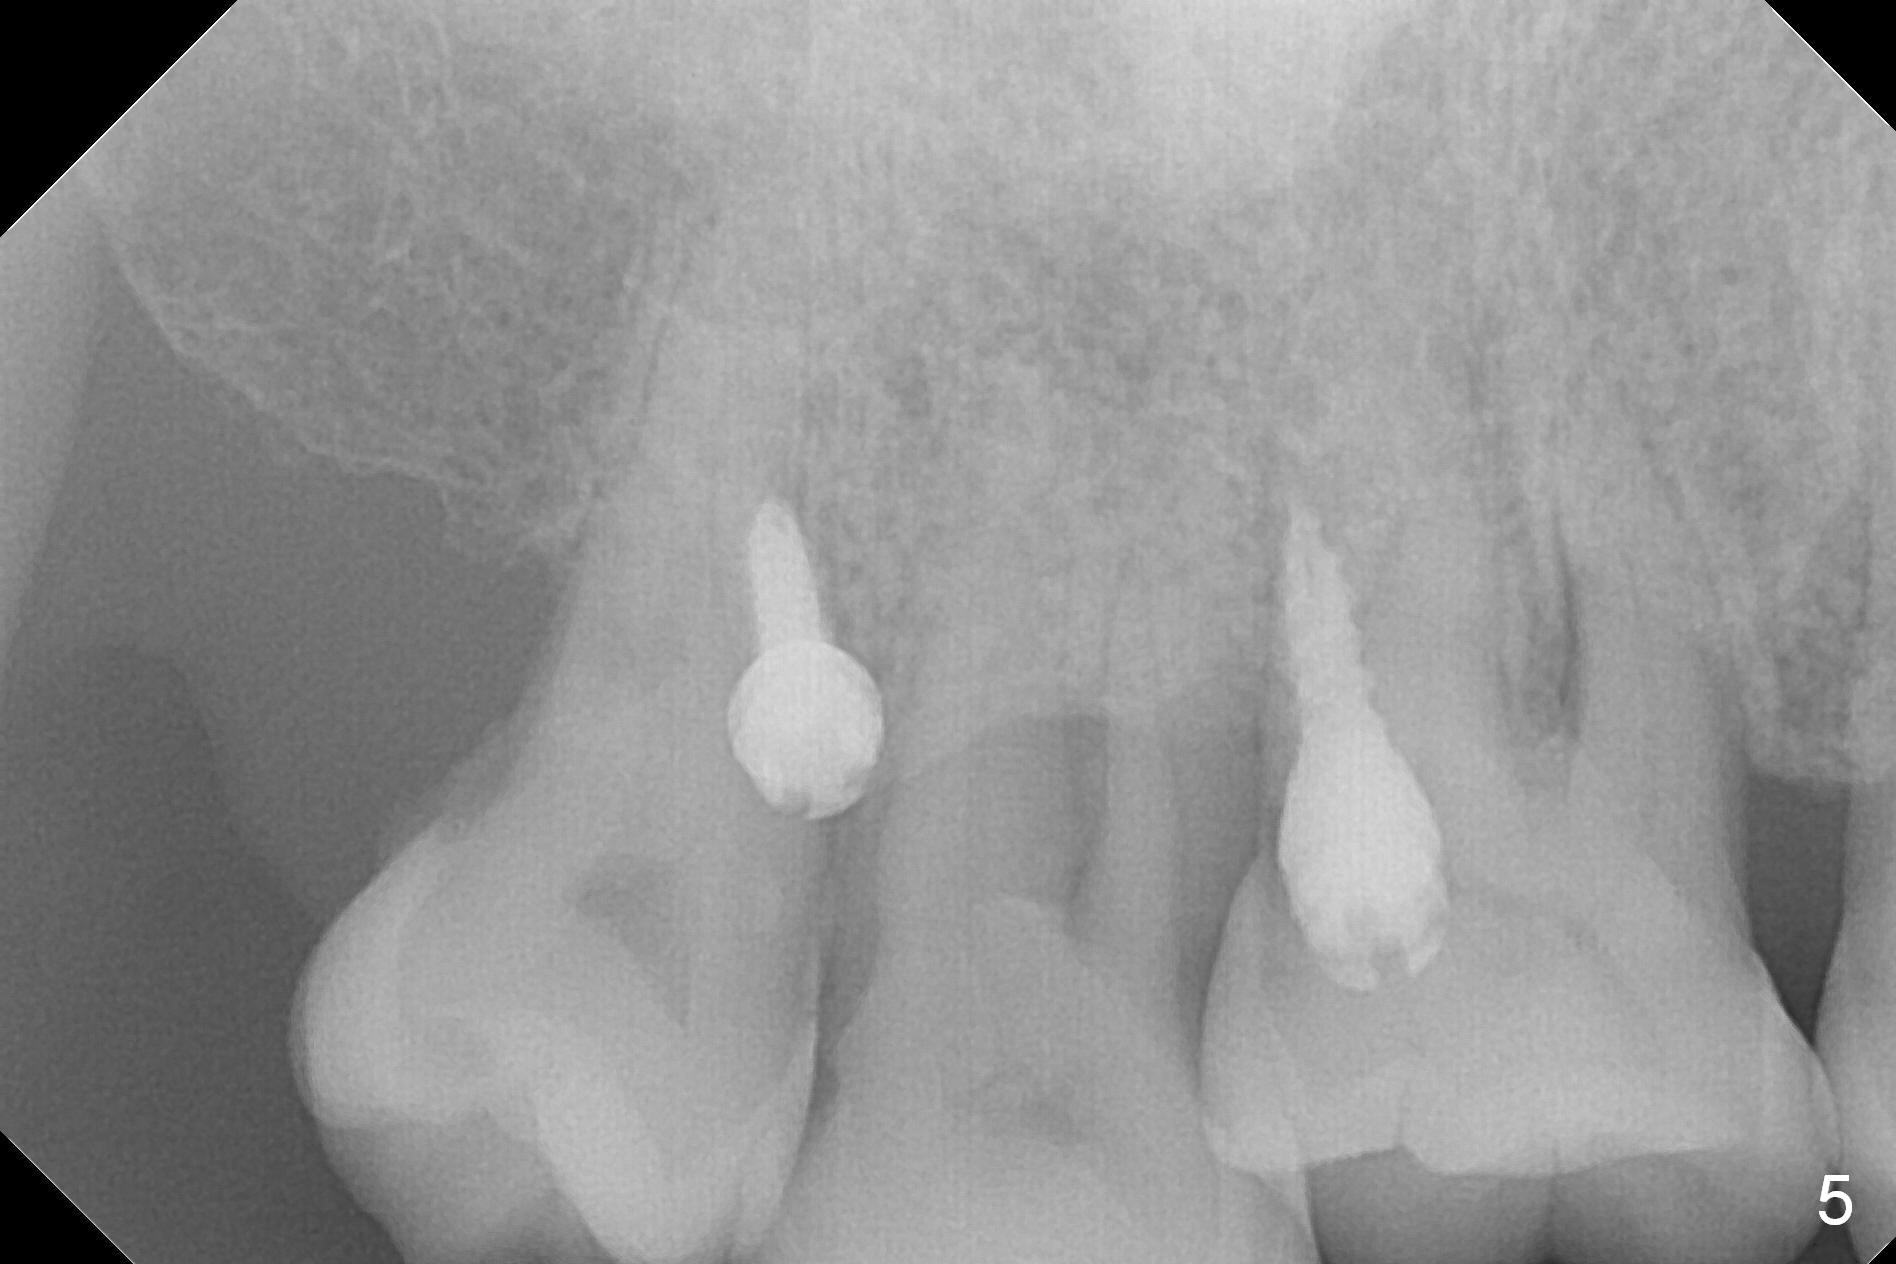

Two days post #31 implant placement, the patient returns for orthodontic intrusion of the tooth #2 with mini-implants (Fig.1). The palatal cusps have been trimmed (Fig.2 ^), since they almost contact a healing abutment at #31(*, Fig.3). Two mini-implants are to be placed mesiobuccal and distopalatal to the affected tooth. After minimal injection of Lidocaine, a 1.6x6 mm Tomas implant is placed in full length mesially (Fig.4), while the other (1.6x8 mm) half way (Fig.4). Following change in implant site mesially (Fig.6 >), the implant is half inserted (Fig.5). It appears that the tip of the distal implant is toward the tooth #1 (Fig.5). After withdrawing the implant partially, it is re-directed to apparently ideal trajectory (Fig.7). Ideally the mesial implant (Fig.8) should have been placed partially initially (Fig.4,5,7) so that the trajectory could have been able to be changed.